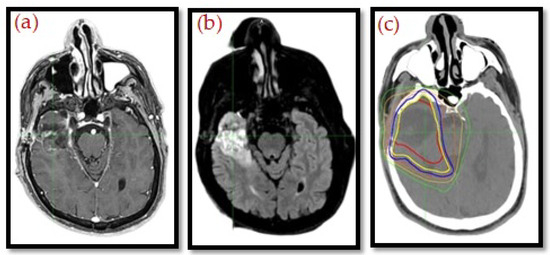

MRI integration is also at the heart of adaptive radiotherapy. MR-Linac systems provide real-time visualization during treatment so that on-table plan adjustments can be made according to daily anatomical changes, as presented in Figure 2 and Figure 3. This feature improves personalization and accuracy and, quite possibly, therapeutic outcomes, and it reduces toxicity. The geometric distortion, protocol standardization, and integration of CT-based dose calculations are also important. Nevertheless, MRI is creating a new paradigm in “head to toe” radiotherapy planning, with increasing evidence supporting its function in precision oncology [20,21,22].

Figure 3. Contrast-enhanced fat-saturated T1w (a) and STIR-weighted images (b) and related centering CT (c), with the superimposed distribution of doses, GTV (red line), and PTV (blue line), in a patient affected by oral floor squamous cell carcinoma [19]. The colored lines represent isodose distribution.